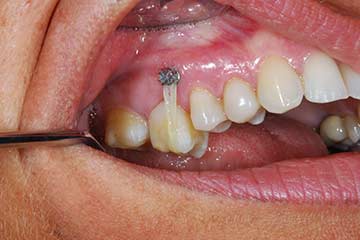

I denti irrecuperabili dell'arcata superiore ed inferiore del paziente di anni 65

sono stati sostituiti da 10 impianti, cioè protesi radicolari endo-ossee che sostengono le protesi fisse superiore ed inferiore.